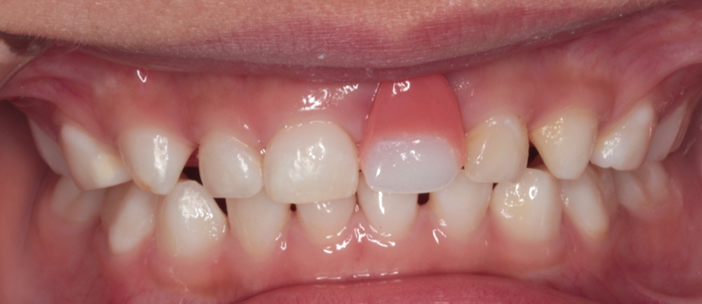

- 来院の理由

- 前歯のケガの後、歯茎が腫れてきた(矢印部)

- 治療期間

- 3-4年(ケガした年齢によります)

- 治療内容について

- 前歯のケガの後、歯の神経が弱り、歯の根が急速に吸収して腫れてしまうことがあります。残念ながら、歯を残すことは難しく抜歯となりました。永久歯が生えるまで3-4年ほどありますので、抜歯したスペースを維持するために小児用の入れ歯(義歯)を使うこともできます。 自費診療となります。